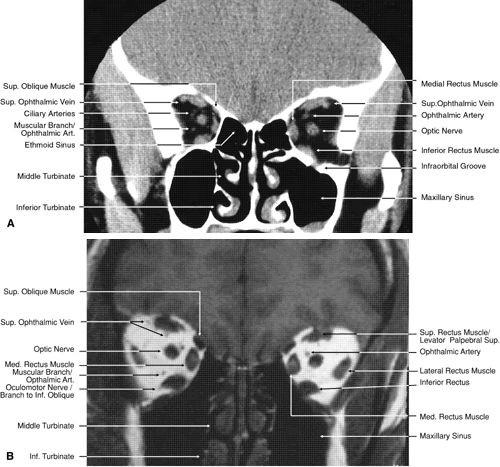

Fig. 19. Coronal images through midorbit posterior to the globe. A. Computed tomography scan.B. T1-weighted magnetic resonance imaging.

Fig. 20. Coronal images through orbital apex. A. Computed tomography scan. B. T1-weighted magnetic resonance imaging. C. Anatomic section of a cadaver head at the level of the orbital apex.

The globe is shown in Figure 12. The orbit and periorbital structures are shown in Figures 13 through 16, and the optic canal is shown in Figures 17 through 26. The cavernous sinus and optic chiasm are shown in Figures 27 and 28, and the posterior visual pathway and cranial nerves are shown in Figures 29 through 33.